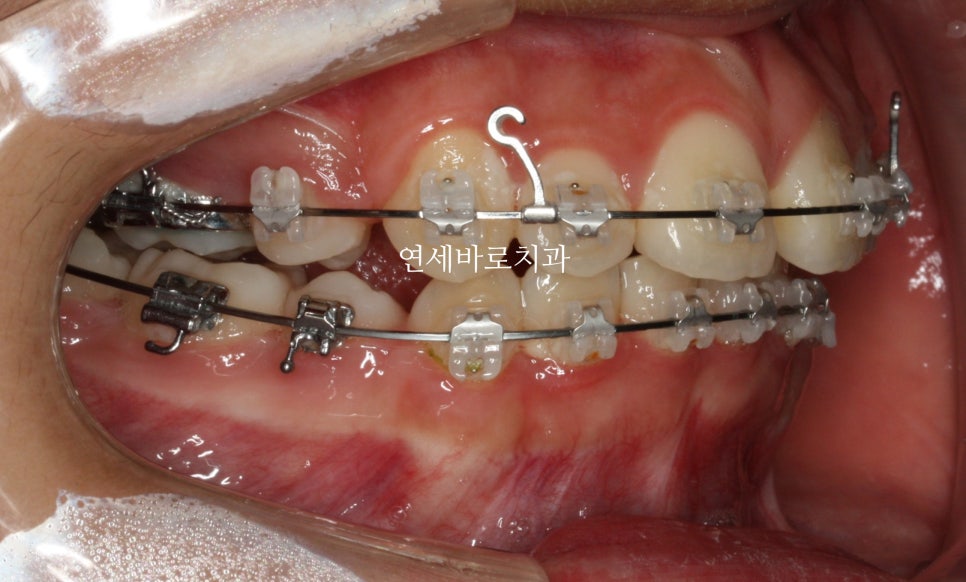

1) 어금니쪽 교정장치는 어디회사 제품을 사용하나요?

2) 와이어는 어디회사 제품인가요?

3) 파워체인은 어디회사 제품인가요?

하지만 안보이는 것들이 더 중요한 것이 교정치료입니다.

특히 와이어와 파워체인은 너무나도 중요합니다.

저가의 중국산 와이어와 파워체인은 제가 사용하는 것에 비하면 거의 1/10 또는 그 이하의 가격입니다.

그걸로 교정치료를 하면 치료기간이 매우 길어집니다.

그리고 치근 흡수 등 다양한 부작용이 잘 생깁니다.